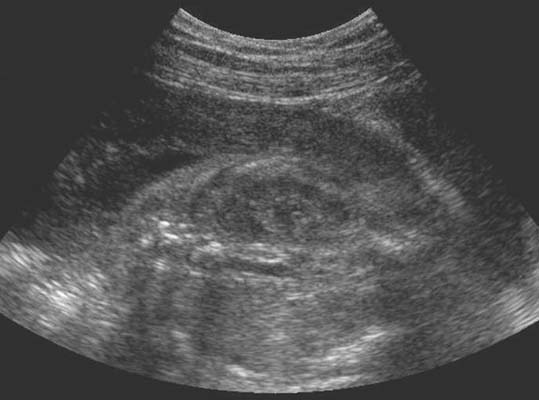

Sur une coupe transversale, deux lacunes de part et d’autre du rachis. Image obtenue plus tardivement en coupe longitudinale (17 – 18 SA).

En coupe longitudinale (de dehors en dedans), aspect en haricot :

*Capsule rénale : fine mais très échogène, permet de suivre le contour du rein.

*Parenchyme rénal : peu échogène, épais de 8 à 10 mm en fin de grossesse. On dissocie la médullaire ou les pyramides sont presque vides d’écho sans liseré et la corticale plus échogène représentée par de fins échos denses et homogènes